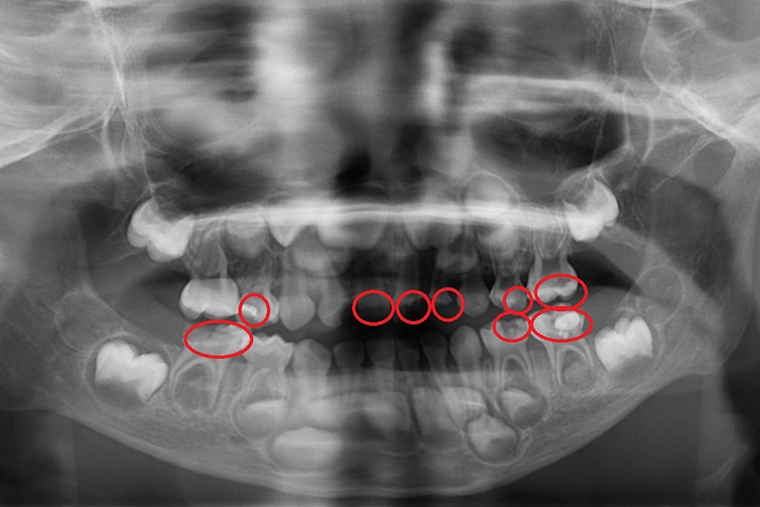

一位5歲的小宏在幼兒園定期接受塗氟和口腔檢查,日前卻出現牙痛、臉頰腫脹,台北慈濟醫院兒童牙科醫師陳默檢查發現,小宏罹患嚴重齲齒並已引發蜂窩性組織炎,雖然積極治療,但最後不得不拔除4顆已無法補救的乳牙。陳默醫師對此表示,學校塗氟無法取代完整的牙科檢查與X光診斷,家長應該自孩子長牙後就要定期帶至牙科門診檢查,並掌握5大護牙關鍵,勿等蛀牙惡化才就醫。

【NOW健康 林郁敏/新北報導】一位5歲的小宏在幼兒園定期接受塗氟和口腔檢查,日前卻出現牙痛、臉頰腫脹,台北慈濟醫院兒童牙科醫師陳默檢查發現,小宏罹患嚴重齲齒並已引發蜂窩性組織炎,雖然積極治療,但最後不得不拔除4顆已無法補救的乳牙。陳默醫師對此表示,學校塗氟無法取代完整的牙科檢查與X光診斷,家長應該自孩子長牙後就要定期帶至牙科門診檢查,並掌握5大護牙關鍵,勿等蛀牙惡化才就醫。

孩子的第一顆乳牙多在出生6至8個月時萌發,許多家長認為乳牙會自然脫落,不需要特別治療,或認為學校塗氟即可預防蛀牙,未定期帶孩子就醫。實際上,乳牙琺瑯質較薄,一旦蛀牙發生,進展速度遠快於恆牙,且嬰幼兒無法清楚表達不適,常在牙齒嚴重腐蝕、甚至感染發炎後才被發現。

4.定期至牙科檢查:雖然學校會定期塗氟,但礙於環境及燈光,執行醫師未必每次都能清楚檢查牙齒狀況,因此即使孩子沒有牙痛或明顯異常,也應至少每半年至專業的兒童牙科進行檢查,以利及早發現肉眼難以察覺的齲齒。